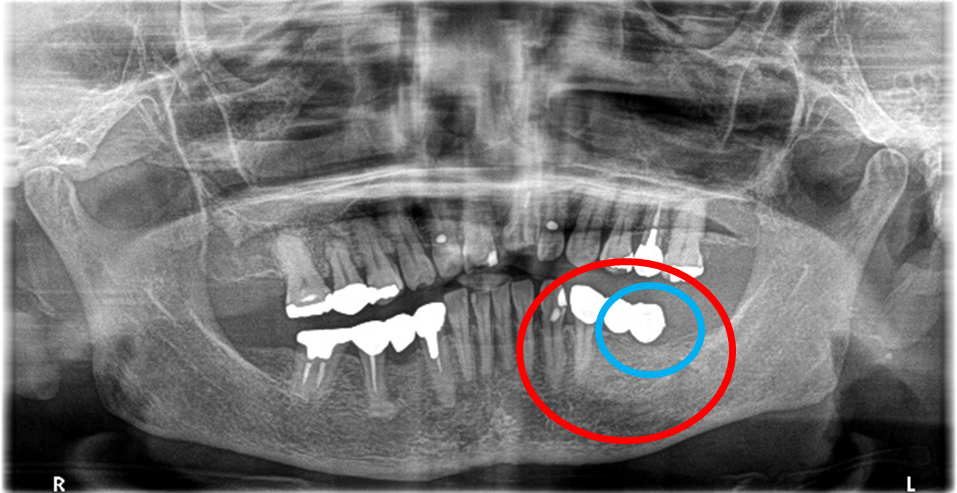

今年の1月、70歳代女性のYさんが来院されました。

「右下の1番後ろの歯が浮いたような感じで、グラグラしていて噛むと痛みもあります。」とのこと。レントゲンで詳しく調べると、噛み合わせの問題と歯周病の進行が原因で、奥歯の周りの骨がなくなってしまっていました。この歯は残念ながら抜歯になることをYさんにお話しし、他の歯が多く残っているので、インプラント治療をおすすめしました。(インプラントは他の歯に負担をかけないので、残っている歯を守ることができます。)

この時はYさんはしばらく様子を見ることにされましたが、5月に再び来院され、「インプラントをお願いします」と決心してくださいました。合計2本のインプラントを入れ、Yさんは、「左右の歯で食べ物が噛めるようになり本当に良かったです。今後も歯を大切にしたいと思います。」と、とても嬉しそうにされていました。